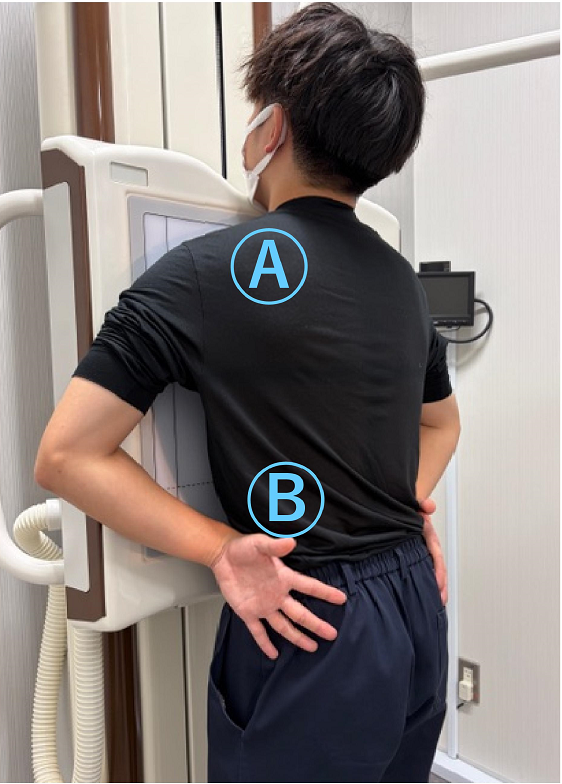

理想的なポジショニングのご紹介

ポイント① アゴを上に向けて、体を装置に近づける

Ⓐアゴは軽く上向き

台に載せなくてもOK!

(背伸びはNG)

Ⓑ手は腰の横

手の平は外向き

ポイント② 肩と肘をできるだけ前(装置側)へ

応用編 手を装置の横へ伸ばし、手のひらを外側にむける

Ⓐ肩はできる限り装置に近づける

Ⓑ手のひらを外側に向けることで、

肩甲骨が肺と重ならない姿勢になります

必要に応じて撮影する技師がポジショニングのお手伝いをさせていただきます。